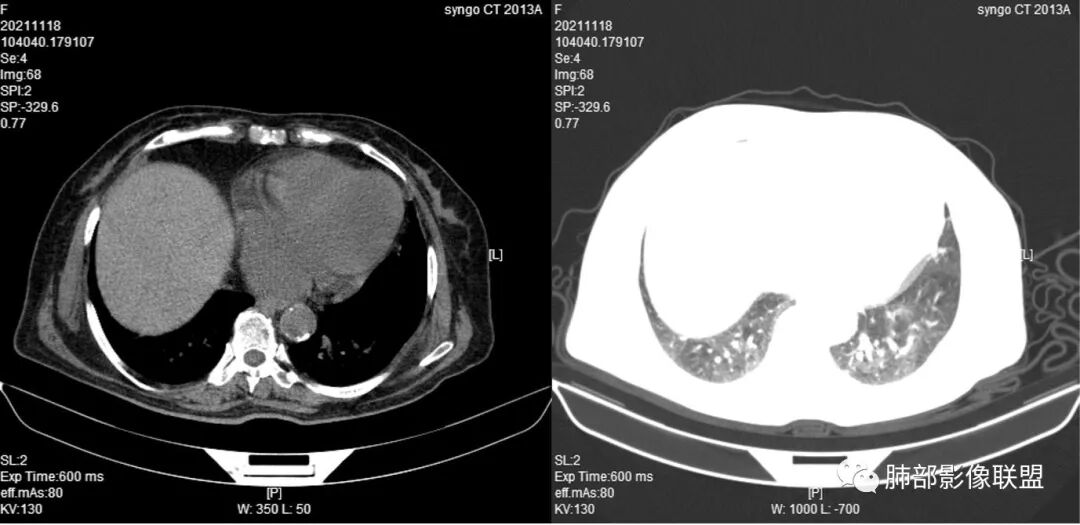

抗真菌治疗1月后复查

3.实验室培养出多种病原菌,并针对性覆盖多种抗感染药物,但肺部病灶却不断进展。

4.白血病化疗后,CT上出现多发结节,边缘可见晕征,病灶内可见多发坏死,右肺中叶肺动脉可见充盈缺损,右肺中叶可见融冰征,右肺中叶肺动脉侵犯栓塞伴右肺中叶肺梗死,可符合真菌感染。